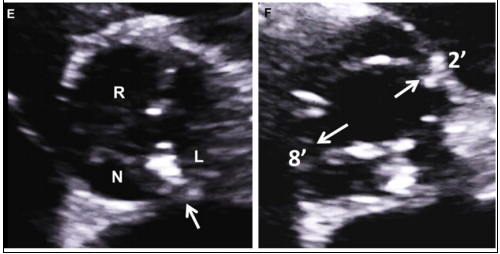

正常主动脉瓣由3个半月瓣组成,称三叶式主动脉瓣(tricuspid aortic valve, TAV),根据瓣膜位置及冠状动脉开口可将其分为左、右和无冠状动脉瓣。而BAV因主动脉瓣发育异常导致相邻两个半月瓣形成融合瓣,部分融合瓣上可见融合嵴,使瓣叶不对称。

Sievers分型

Sievers分型广泛应用于临床,根据融合嵴的数量将BAV分为3型:Type 0型(无嵴)、TypeⅠ型(1个嵴)和TypeⅡ型(2个嵴),其中最常见的是TypeⅠ型,约占90%。根据嵴的空间位置又分为左右冠窦融合型(RL型)、右无冠窦融合型(RN型)、左无冠窦融合型(LN型),其中RL型最常见,约占80%。

最新国际共识认为仅基于外科角度的Sievers分型仍有局限性,因此新的分型为:融合型、双窦型和部分融合型。其中融合型最常见,占90%~95%,相当于TypeⅠ型。双窦型BAV并不常见,占5%~7%,由大小、形状大致相同的两个瓣叶构成,分前侧对侧表型和前后表型(图b)。部分融合型的流行率尚不清楚,表现为典型的三叶瓣膜,但在连合底部可见<50%的瓣尖融合。至于Sievers分型中的Type Ⅱ型,共识认为称单叶瓣较为合适。

双窦型